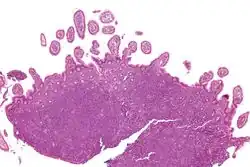

| Micrograph showing mantle cell lymphoma (bottom of image) in a biopsy of the terminal ileum. H&E stain. | |

The history and physical examination may reveal some of the signs and symptoms consistent with Mantle Cell Lymphoma. Biopsy of the involved tissues (such as the lymph nodes, bone marrow, gastrointestinal tract, spleen or other areas) shows the characteristic histopathologic changes of MCL. There are distinct growth patterns of MCL seen on biopsy; these include the diffuse type, nodular type, mantle zone lymphoma and in situ mantle cell lymphoma.[8] In the diffuse growth pattern, there is a diffuse growth of lymphoma cells throughout the lymph node resulting in effacement of the architecture of the lymph node.[8] In the nodular type, there are large nodules of MCL cells in the lymph node with no germinal centers observed.[8] In MCL with expansion of the mantle zone, the lymphoma cells cause expansion of the mantle zone around normal germinal centers.[8] And in MCL in situ, the lymphoma cells are contained within the mantle zone without expansion.[8] Histologically, the lymphoma cells in classic MCL are characterized as small to medium lymphocytes with scant cytoplasm and clumped chromatin with prominent nuclear clefts and the nucleoli are not visible.[8] There are cytologic subtypes; the blastoid subtype, is characterized by round nuclei, fine chromatin with some distinct nucleoli.[8] The pleomorphic subtype is characterized by nuclei that vary in size and shape with some having a cleaved form.[8] The blastoid and pleomorphic subtypes of MCL are associated with a more aggressive course.[8]